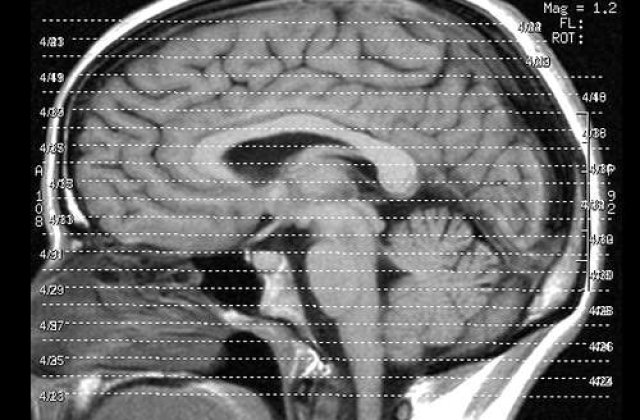

Lewis suferea de o boala rara numita encefalita Rasmussen, iar analizele aratau ca boala i-a afectat jumatatea dreapta a creierului si ameninta dezvoltarea normala a acestuia. In acel moment, doctorii au hotarat ca singura solutie ar fi indepartarea acelei jumatati de creier in speranta ca partea stanga va prelua anumite functii importante a partii extirpate.